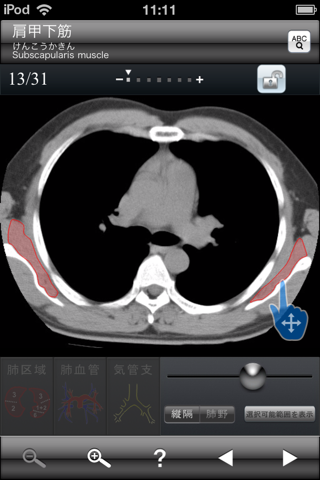

・調べたい場所を指カーソルで示せば解剖名が表示されます。

撮影画像:肺野条件、縦隔条件

解剖名数: 15(肺野条件)、66(縦隔条件)